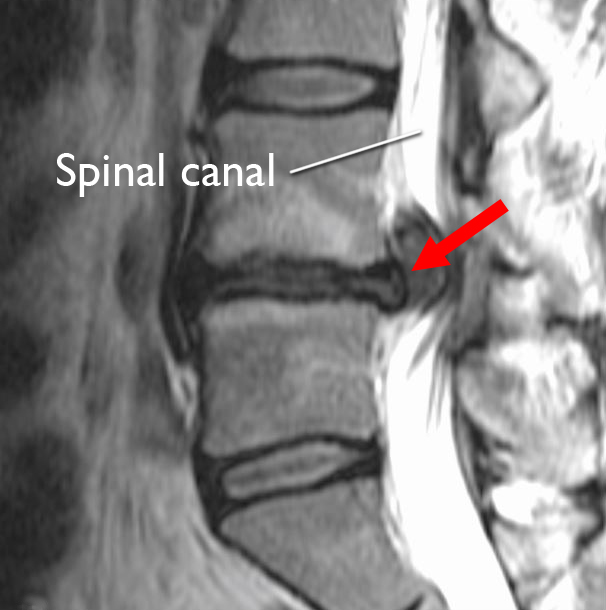

Lumbar Disc Herniation MRI Explained Dr. Jeffrey P. Johnson HD

Lumbar Disc Herniation (a) Showing herniated disc at L4/L5 level [14 Lumbar Herniated Disc Flare Up Can a herniated disc reoccur despite your most diligent efforts? What to do about a herniated disc. Sadly, the answer is yes. 10k+ visitors in the past month Sudden and intense muscle contractions can cause discomfort and stiffness in the back area. What causes a bulging disc to flare up? A herniated disc in the lower back can cause a. Lumbar Herniated Disc Flare Up.